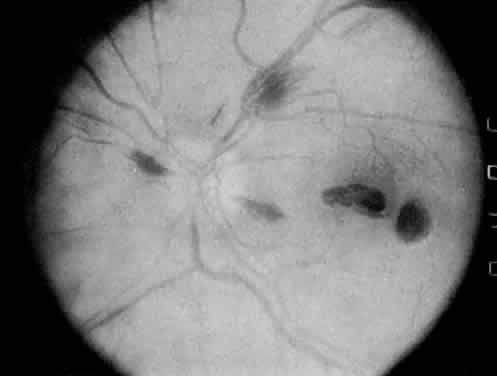

The classic ocular finding in DIC is serous retinal detachment64,65 (Fig. 5). The pathogenesis of these detachments involves choriocapillaris occlusion resulting in retinal pigment epithelial damage and subsequent loss of retinal pigment epithelial barrier and pump function. Fluorescein angiography confirms this pathophysiology, showing delayed filling of the posterior choroid with later pigment epithelial staining (Fig. 6). If the underlying DIC can be reversed, the retina may reattach, with return of vision. Other findings associated with DIC include retinal and vitreous hemorrhages.

Fig. 5. Serous retinal detachment in disseminated intravascular coagulation. (Hoines J, Buettner H: Ocular complications of disseminated intravascular coagulation [DIC] in abruptio placentae. Retina 9:107, 1989.)